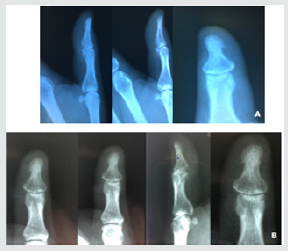

Figure 3: A: Right hand radiograph. Made on March 14, 2018 without pathology; B: radiography of the first right-finger on June 14, 2018.

Patient underwent radiography on March 14, 2018 and Magnetic Resonance Imaging on March 15, 2018, of the right hand both after lesion excision and biopsy result. Presented the following results: right hand radiograph (examination performed on March 14, 2018): no alterations; Resonance of the right hand (examination performed on March 15, 2018): no changes. Patient returns to the unit after complete excision of the nail and result of the biopsy. It reports slight local sensitivity, in use of Rifamycin, topical. The anatomopathological of July 13, 2018, presented the following result: material: I - Nail matrix and Grocott staining (fungi). II - Fragment of nail. Macroscopic Examination: I-Fragment of fabric, gray and shiny, measuring 0,8x0,5cm. II - Fragment of brown nail, measuring 1.8x0.6cm. Diagnosis: I-Nail bed with fibrosis and chronic inflammatory infiltrate. Fungus research (GMS) is negative. II-Nail tissue with dystrophic alterations. Following the patient during the restoration of the nail plate. Hyperkeratosis returned in the same region, hyperchromic, a new x-ray and a new lateral 1/3 matricectomy were requested and treatment with Terbinafine for Onychomycosis was started.